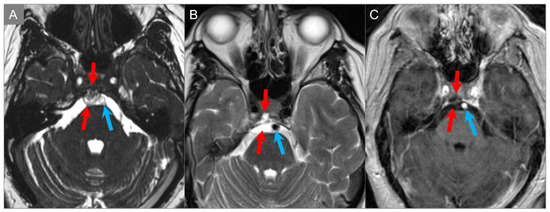

4.1.2. Schwannoma

4.1.3. Metastasis